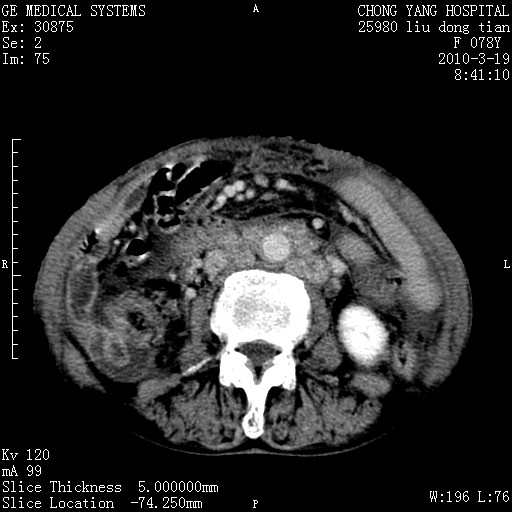

标题: CT25199:F 78Y 腹胀半年 消瘦乏力 [打印本页]

胆囊壁增厚并明显强化,胆囊癌伴多发转移瘤可能性大,淋巴瘤不除外,右肾囊肿,胸腹水.

考虑nhl,肝、脾、腹膜腔及腹膜后多发淋巴结受侵,腹水,右肾囊肿,慢性胆囊炎,右侧少量胸腔积液。

胰头有肿块形成,胰头ca伴肝脾、腹膜腹膜后转移

胆囊有软组织影有强化,支持胆囊癌,肝脾、腹膜后淋巴结转移。

nhl的淋巴结多围绕主动脉,而且主动脉会移位,所以不考虑nhl。

分开来讲:肝左叶、尾叶病灶有不均强化像肝癌;

脾脏病灶无强化,像多发囊肿或淋巴管瘤,不除外淋巴瘤(低强化);

胆囊增生性病变:胆囊癌,腺肌增生症,慢性胆囊炎;

肝门、胰腺头、腹膜后多个团块: 淋巴瘤,转移;

一元论最好了 淋巴瘤所致改变; 胆囊癌转移不像,胆囊周围肝组织清晰,肝癌淋巴结转移?三元论都不止。

最后报的胰头癌多发转移,脾脏单独考虑囊肿或淋巴管瘤。